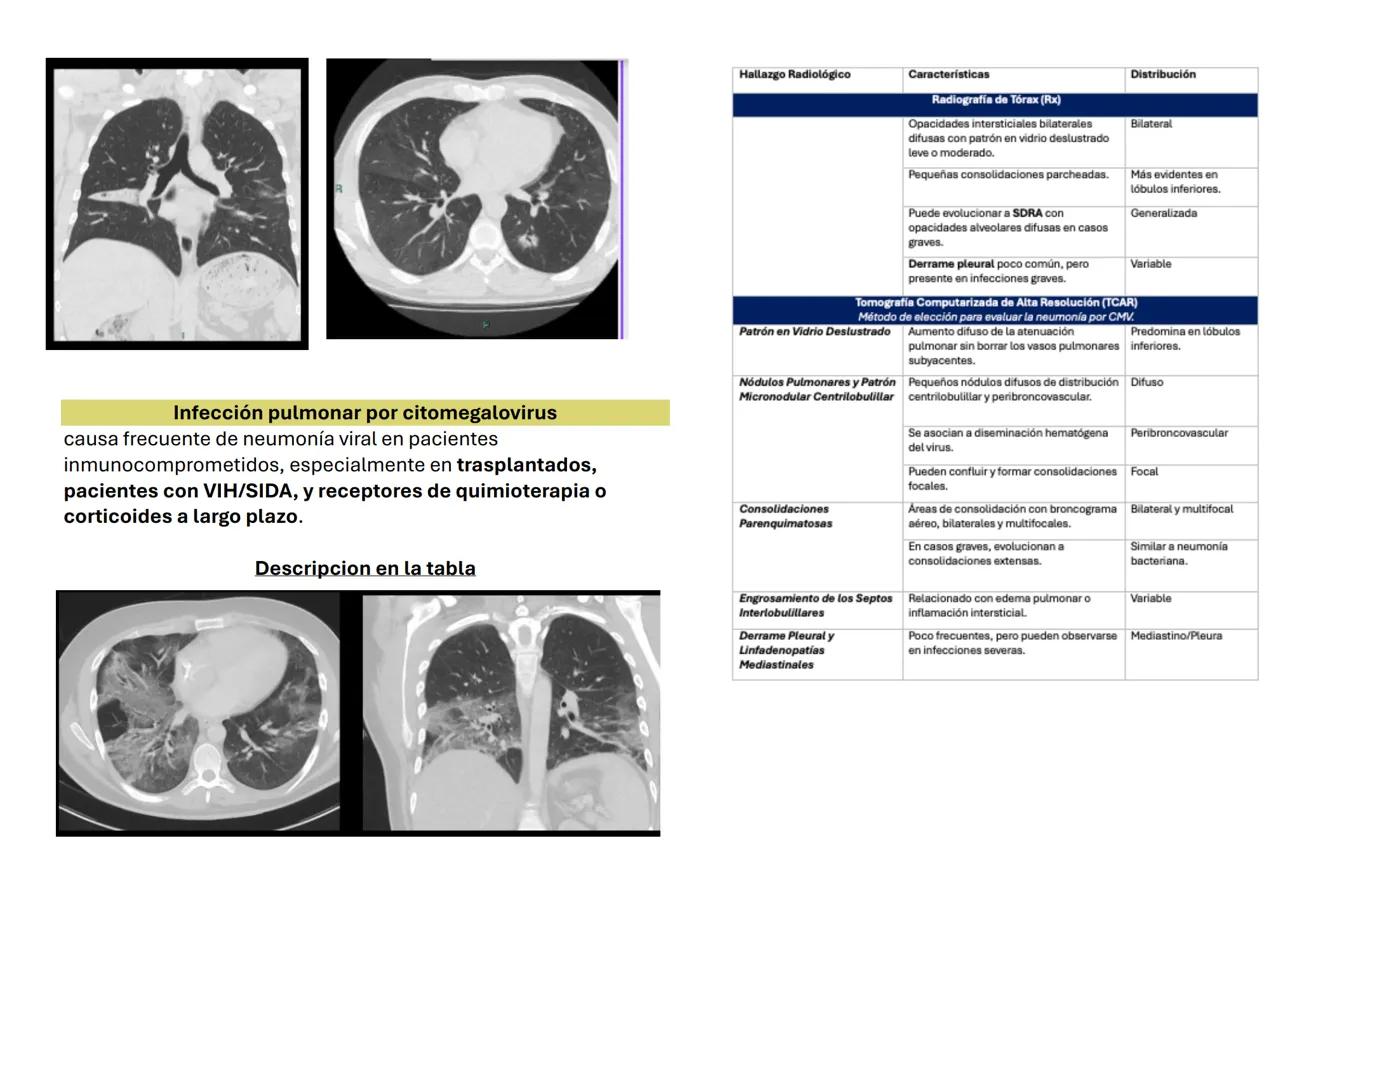

La infección pulmonar por citomegalovirus es especialmente importante en pacientes inmunocomprometidos como trasplantados, pacientes con VIH/SIDA, o quienes reciben quimioterapia prolongada.

En radiografías simples verás opacidades intersticiales bilaterales con patrón en vidrio deslustrado, más evidentes en lóbulos inferiores. Sin embargo, la TCAR es el método de elección para el diagnóstico definitivo.

Los hallazgos más característicos en TCAR incluyen: patrón difuso en vidrio deslustrado sin borrar los vasos subyacentes, pequeños nódulos de distribución centrilobulillar, y consolidaciones parenquimatosas peribroncobvasculares.

💡 Punto importante: A diferencia de otras neumonías virales, el CMV puede evolucionar a SDRA con opacidades alveolares difusas en casos graves.